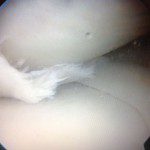

Εικόνα 1. Αρθροσκοπική τεχνική και αρθροσκοπική εικόνα ενός φυσιολογικού μηνίσκου (μέση) και ενός μηνίσκου με ρήξη (δεξιά)